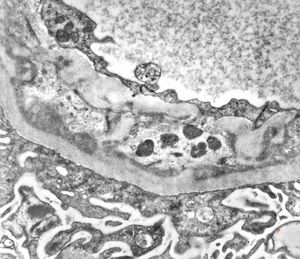

M,17y. | Alport syndrome - split and laminated basement membranes